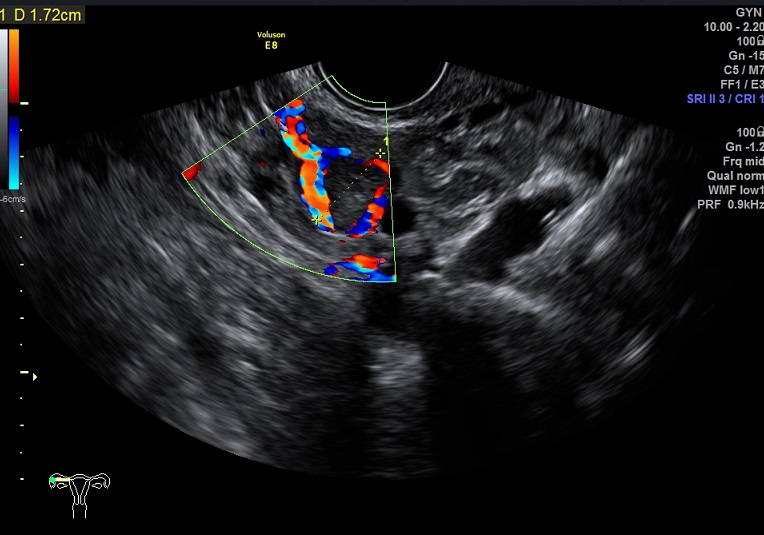

| 女性,25岁,继发性不孕1年余,难免流产4次。 | ||

2015-3-23 月经第19天检查 |

2015-3-23图示